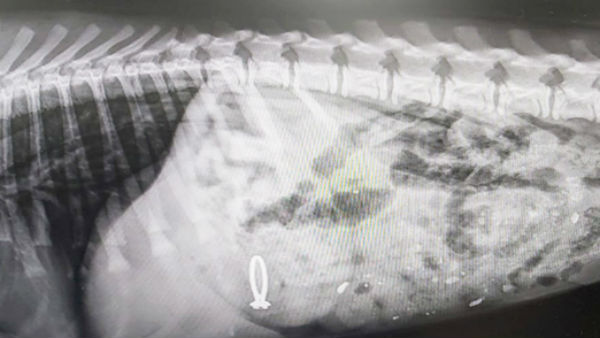

இதனால் அதிர்ச்சி அடைந்த அப்பெண், அப்போது அங்கு யாரும் வந்திருக்க வாய்ப்பில்லை என்பதால் அந்த மோதிரத்தை பெப்பர் தான் விழுங்கி இருக்க வேண்டும் என முடிவு செய்தார். எனவே உடனடியாக பெப்பரை அவர் கால்நடை மருத்துவமனைக்கு அழைத்துச் சென்றார். அங்கு பெப்பருக்கு எக்ஸ்ரே செய்து பார்க்கப்பட்டது.

அதில், பெப்பரின் வயிற்றில் மோதிரம் இருப்பது உறுதியானது. அதனைத் தொடர்ந்து பெப்பருக்கு உரிய மருந்துகள் கொடுக்கப்பட்டு அது வாந்தியெடுக்க வைக்கப்பட்டது. அப்போது அதன் வயிற்றில் இருந்த மோதிரம் வெளியில் வந்து விட்டது.

நான் எனது அம்மாவின் திருமண நிச்சயதார்த்த மோதிரத்தை விழுங்கி விட்டேன். அதனால் தான் மருத்துவர் வாந்தி எடுக்க சொன்னார். வேறு எதுவும் கேட்கதீர்கள்' என நகைச்சுவையாக பேப்பரே பேசுவது போல் பதிவிட்டனர். கூடவே பெப்பரின் எக்ஸ்ரே படத்தையும் வெளியிட்டனர்.